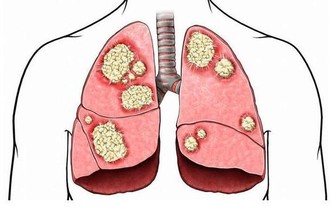

眾所周知,愛滋病是一個危害性極大的傳染病,是由於感染上愛滋病病毒(HIV)而引起的,死亡率很高。有數據表明,全球至少已有3千多萬人死於愛滋病,由此可見愛滋病威力之大。

艾滋病傳播的途徑主要是:與感染者的血液、乳汁、精液、陰道分泌物等多種體液發生交換。